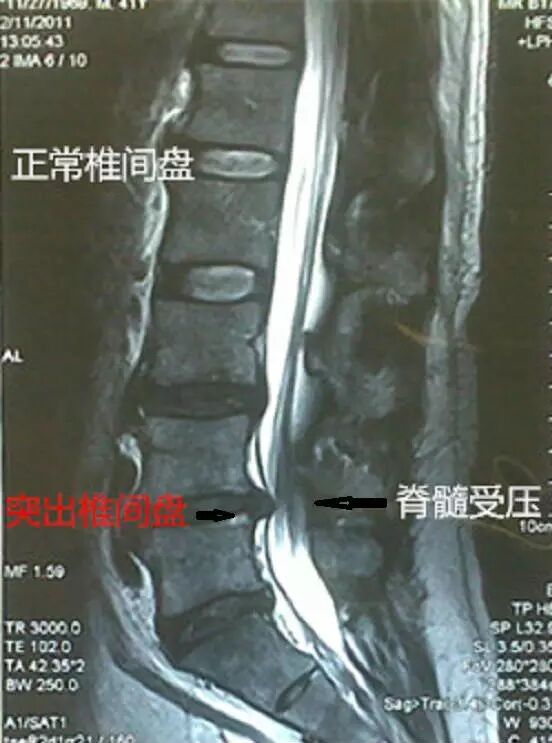

磁共振MRI能显示椎间盘、神经而且无辐射,软组织的分辨能力强,是最重要的检查。(约700元)治疗

严重的腰椎间盘突出,脊髓受压明显,经过规范的保守治疗不能好转的,只能手术切除突出的椎间盘,解除神经压迫,稳定脊柱